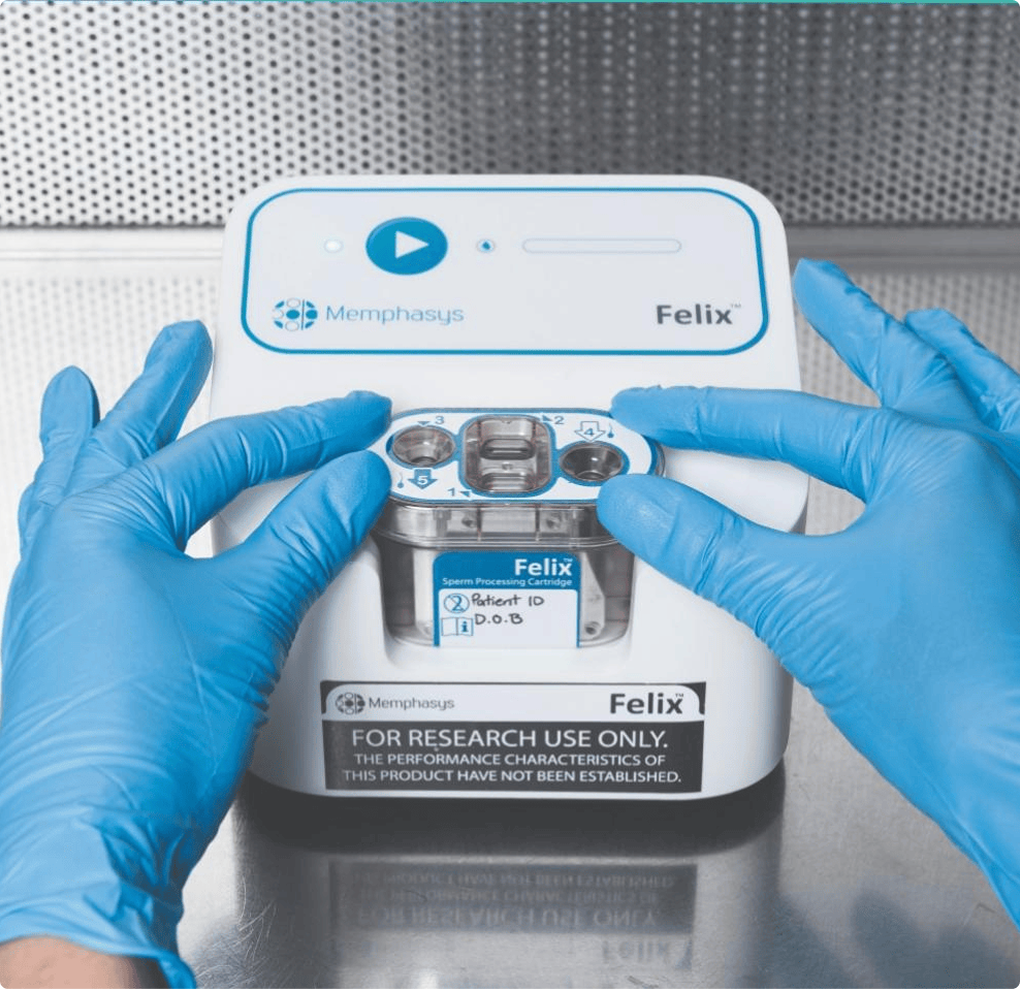

Advancing world-first breakthroughs, faster

World first breakthroughs aren't designed to sit on the lab bench forever. They need to be in the hands of doctors and patients - saving lives and transforming outcomes. We help you get there.

Medical innovations are not one-size-fits-all, so why should your clinical trials be? At Mobius, our team uses their deep expertise to develop a clinical trial strategy tailored for you.